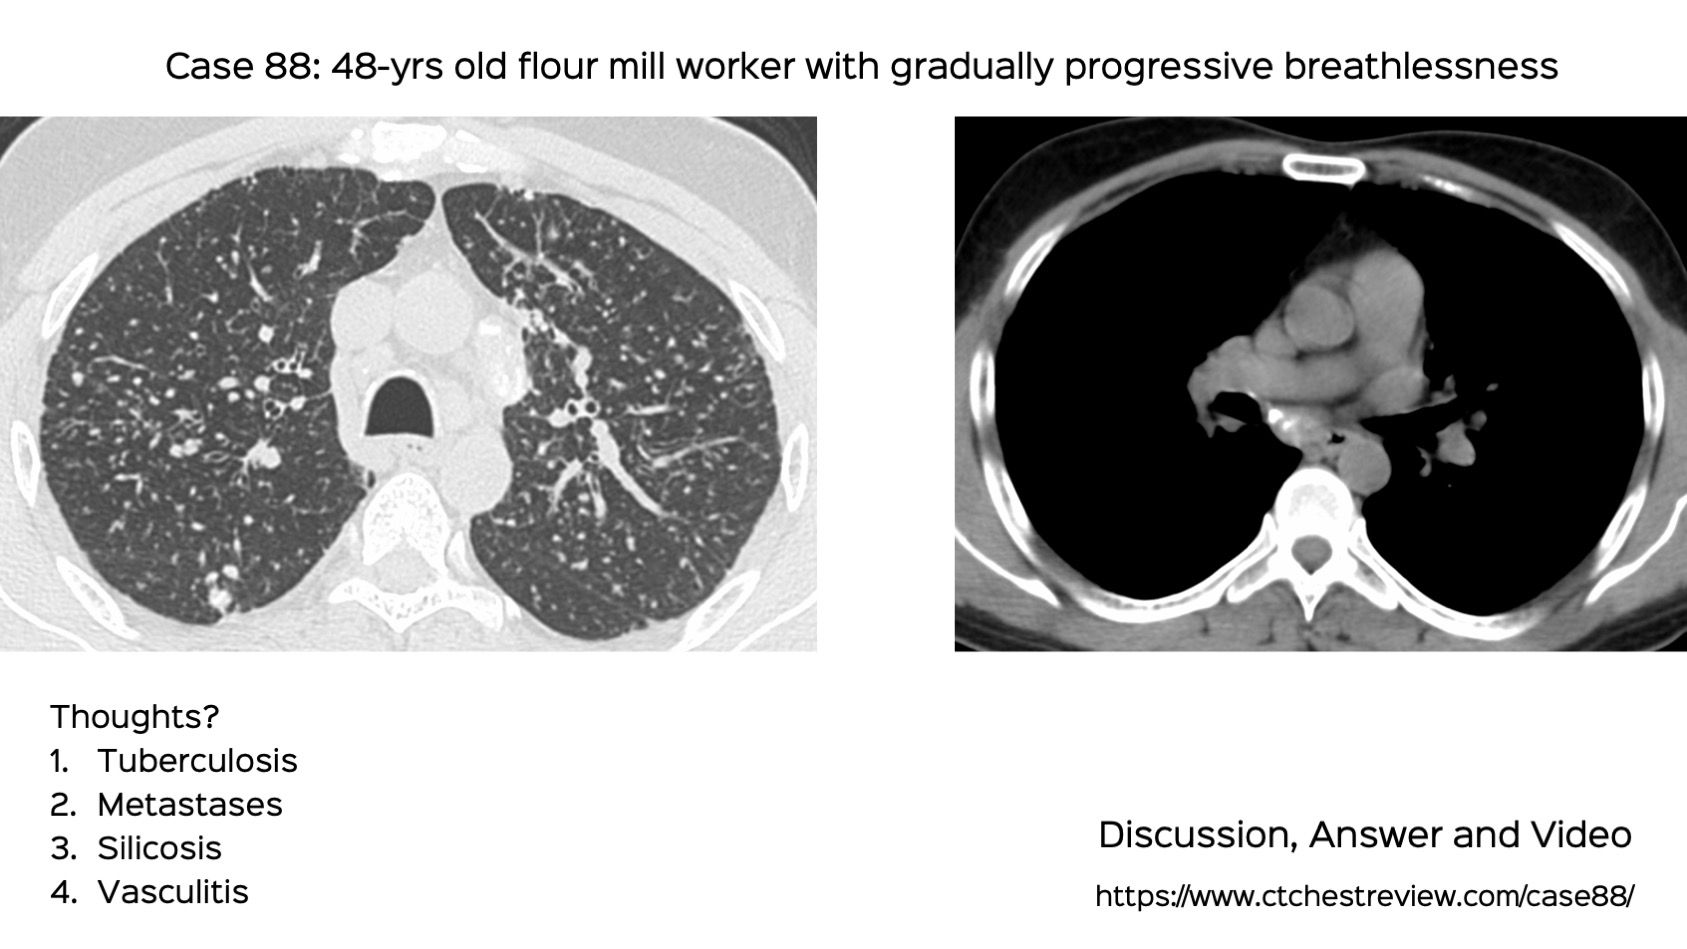

From www.ctchestreview.com

Case 88 Flour Mill Worker Disease Flour Mill Hazards The most severe food safety hazards at flour mills are the physical type. After the wheat proceeds into the mill, scourers, roll stands, sifters, magnets and metal detectors to help identify and eliminate. What are the hazards in grain handling facilities? Unfortunately flour can explode and these explosions, triggered by the ignition of fine dust particles suspended in the air,. Flour Mill Hazards.